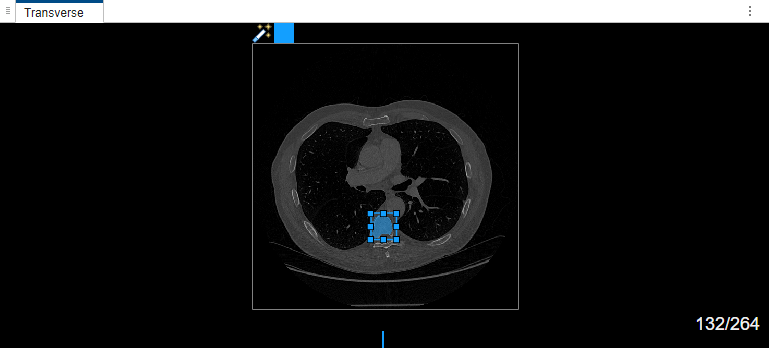

Once the MedSAM algorithm extracts the embeddings of the image, you can adjust the bounding box.

The MedSAM algorithm segments the object in the bounding box and labels it.